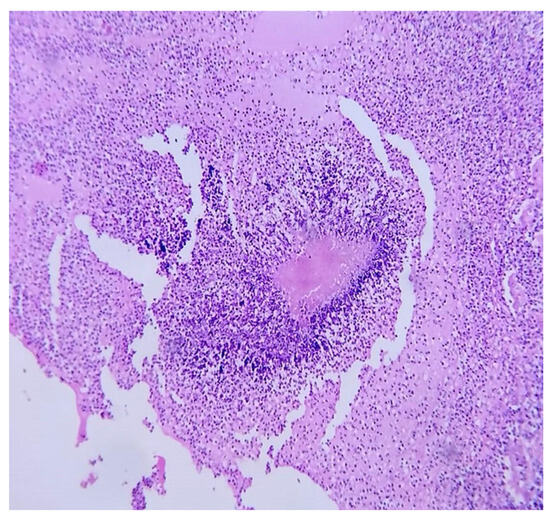

A few weeks later, the histopathological report of renal abscess showed filamentous bacillary structures arranged in a radial and disordered manner, deposit of eosinophilic material, and sulfide structures presumptive of Actinomyces spp. in hematoxylin-eosin staining (Figure 4), and due to the inconclusive diagnosis of malignancy, it was decided to adapt antibiotic therapy to amoxicillin at 2 g orally every 12 h for 6 months with good clinical evolution.

Figure 4.

Microscopic renal abscess: hematoxylin-eosin staining at 40×, where leukocyte infiltration is observed in the interface with filamentous bacillary structures arranged in a radial and disordered manner and a deposit of eosinophilic material.